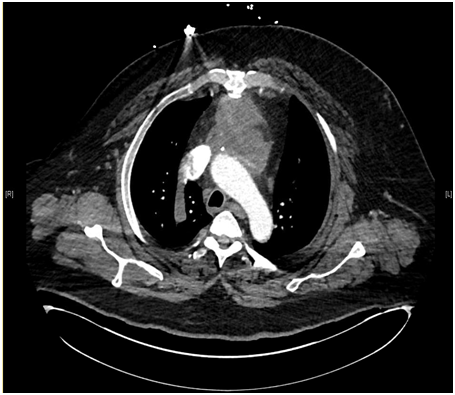

A 57-year-old white male patient with known history of coronary artery disease, morbid obesity, obstructive sleep apnea, hypertension, hyperlipidemia, atrial fibrillation, and tobacco use, presented to a local emergency room with a sudden sharp right arm pain, followed a few hours later by numbness of the right hand. His physical exam was normal except for a very weak pulsation of the right brachial artery. His initial workup included a normal chest x-ray with no acute cardiopulmonary process. A doppler ultrasound of the right upper extremity indicated thrombosis with near-complete occlusion of the distal right brachial artery. He was urgently seen by vascular surgery and underwent thrombectomy of the distal right brachial artery thrombus that was sent for pathology. Hematoxylin Eosin stain and Grocott’s methenamine silver stain showed fungal organisms identified at the thrombus, that had thin septate hyphae with regular branching and that were morphologically consistent with Aspergillus species (Figures 1-6). Subsequently, he was started on intravenous voriconazole, after his EKG, liver function tests were evaluated revealing a normal QTc interval, and liver enzymes respectively. Patient was then evaluated for evidence of disseminated Aspergillosis. His blood cultures have been negative. Aspergillus galactomannan antigen was negative, and his HIV ½ Antibody screen was negative. A computed tomography (CT) scan of the chest with angiography showed an ascending aortic pseudoaneurysm with large soft tissue component, representing a mycotic aneurysm. The contrast opacified lumen of the pseudoaneurysm measured 2.8 x 3.8 cm and there was a portion of the pseudoaneurysm more superiorly that was thrombosed measuring 6.3 x 7.2 cm (Figures 7 & 8). His lungs were clear without evidence of pulmonary nodules or consolidation. CT scan of the brain with contrast and a complete ophthalmological examination were unremarkable. Transthoracic and transesophageal echocardiograms showed no major cardiac finding and no evidence of valvular vegetations. He was then transferred to a tertiary care center where he underwent a homograft of cryopreserved human tissue given the fact that he has an infected mediastinum. He was continued on Voriconazole orally, and he will receive it for life.To note that, five years prior to this event, he underwent an urgent coronary artery bypass grafting (CABG)X3 with reversed autogenous saphenous vein graft from the aorta to the left anterior descending artery, from the aorta to the ramus intermediate, from the aorta to the obtuse marginal artery, along with endoscopic vein harvest left and right greater saphenous veins (from knee to groin bilaterally).

Figure 8 A portion of the pseudoaneurysm located superiorly in mediastinum is thrombosed and measures 6.3 x 7.2 cm.